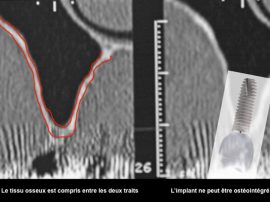

Les photos qui illustrent le texte ont pour unique objectif de vous aider à mieux comprendre les techniques utilisées. Elles correspondent chacune à une réalité qui ne peut être transposée car chaque situation clinique est différente et unique.

L’intervention chirurgicale consiste en une reconstruction osseuse du maxillaire ou de la mandibule avant la mise en place des implants dentaires par votre chirurgien.